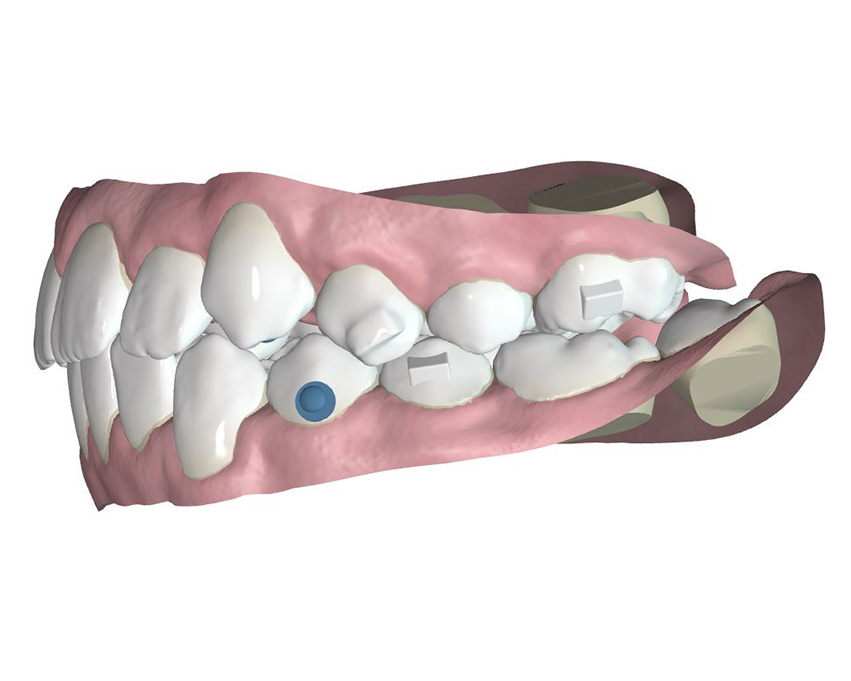

The treatment protocol established for this patient included reciprocal movements: sequential distalization of upper molars, together with protrusion of upper incisors. It is important to point out that the goal in this case was to avoid inclination of upper incisors (proclination) and to achieve movement towards buccal (a range of 4.5mm) to help and gain the needed space for the canine eruption. With the goal of avoiding the disadjustment of the aligner during the treatment, simultaneous to the protrusion a buccal root torque was applied to those tooth of 2 degrees per aligner during that specific movement.

To ensure a good engagement between molars, Dr. Iván Malagón planned constriction and distal palatal rotation in tooth 1.6 ( helped by a vertical mesial bevelled attachment) and applying 12 degrees buccal root torque compensation to tooth 2.6 (planning the movements from the root with Spark approver).

An important tip that Dr. Malagón shares with this case is the fact of avoiding the placement of pontics – that in this case would be eruption guide as it is a growing patient – up until there is enough space. This is a benefit as the TruGEN™ material will be in close contact with the mesial face of 1.4 and distal face of 1.2 and as consequence there will be an optimal control of the tipping of these teeth.